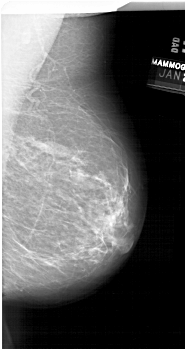

A_1679_1.RIGHT_MLO

RIGHT_MLO LINES 6616 PIXELS_PER_LINE 3511 BITS_PER_PIXEL 12 RESOLUTION 43.5 NON_OVERLAY